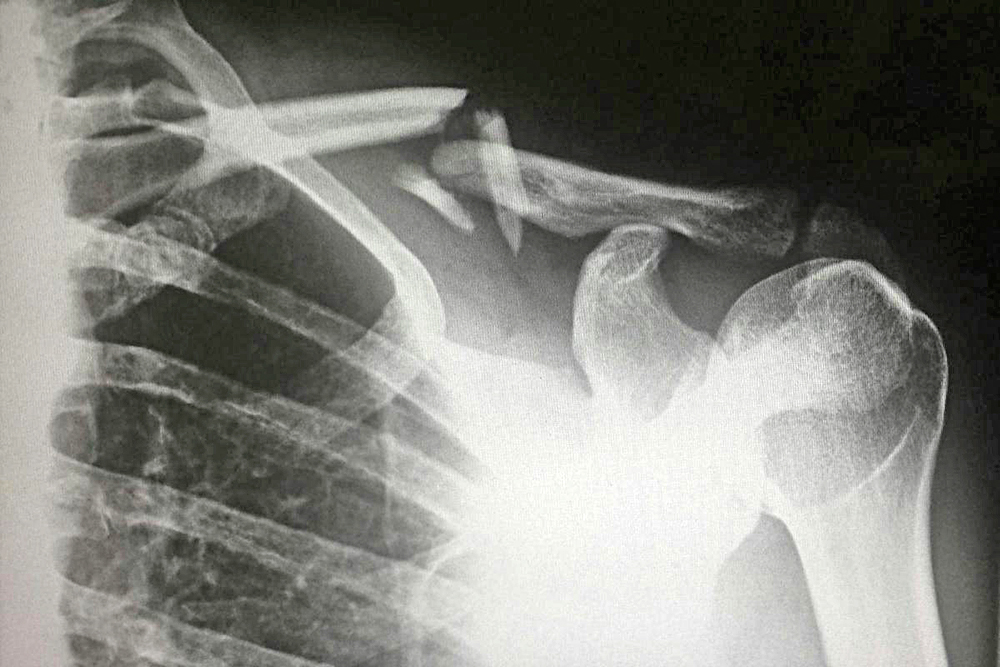

Por otra parte, el segundo caso de sarcoma atípico, atendido por Allenson, fue de un leiomiosarcoma de la vena cava inferior, el cual se caracteriza por ser un tipo de tumor agresivo que crece en órganos adyacentes y tiene un alto potencial de metástasis, ubicado por el oncólogo, en el revestimiento musculoso liso de la pared de la vena más grande del cuerpo, la cual irriga sangre desde las extremidades inferiores del cuerpo al corazón.

El experto señala que estos tumores son sumamente raros; mundialmente sólo se han reportado 400 sarcomas de este tipo. Referente con su tratamiento, Allenson le comentó al equipo de NotiPress, “la cirugía es la única terapia potencialmente curativa”, sin embargo, destaca que el procedimiento para tratar éste, representó un desafío técnico considerable, pues resecar el tumor y reconstruir la vena manteniendo la permeabilidad del flujo venoso, requirió de utilizar diversas tecnologías simultáneamente.

Pese a ello, la junta de expertos determinó que la paciente debía ser sometida a cirugía resección multivisceral compleja, que resultó exitosa. En ésta, el doctor, Allenson y el doctor Charudatta Bavare, cirujano vascular del Hospital Houston Methodist, obtuvieron un control proximal y distal para acceder a los vasos sanguíneos. Posteriormente, extirparon el tumor en su totalidad y colocaron un parche pericárdico bovino, un injerto biológico obtenido del revestimiento procesado del corazón de una vaca, para restaurar la integridad de la vena cava.